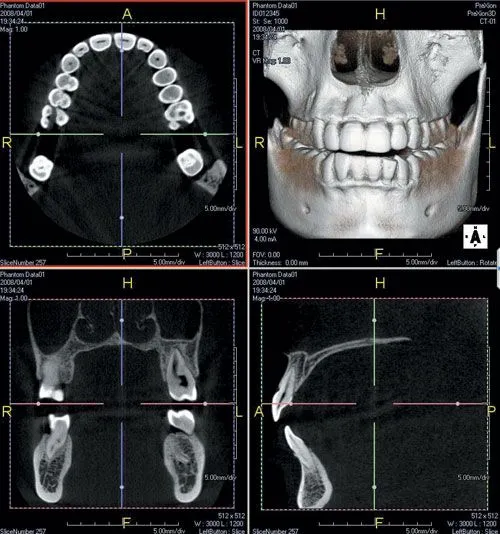

We routinely use our Prexion 3D Cone Beam Computed Tomography (CBCT) system in the assessment and planning for the placement of dental implants.  In 2012, the American Academy of Oral and Maxillofacial Radiology (AAOMR) recommended that cross-sectional imaging be used for the assessment of all dental implants sites and stated that CBCT is the imaging method of choice for gaining this information.  Our use of the Prexion 3D CBCT fully conforms with these recommendations.

Cone Beam Computed Tomography (CBCT) is a imaging technique that is used to generate a 3 dimensional image.  The technology was first introduced into the United States in 2001 and has become increasingly important in the treatment planning involving dental implants.  CBCT scans are fast and comfortable for our patients as nothing is even inserted into the mouth.

In just 17 seconds, our Prexion 3D system will acquire 512 individual views that are reconstructed into a 3D image of the patient's jaw anatomy.  This image can be used to access the height, width, and density of the bone at potential dental implant placement sites.  This information is important to ensure that implants are placed in the safest possible manner with the highest possible success rates.